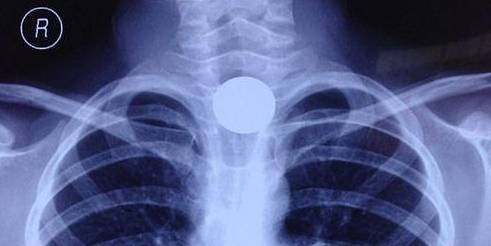

又一个孩子丧生,已致8名儿童身亡!马上检查家